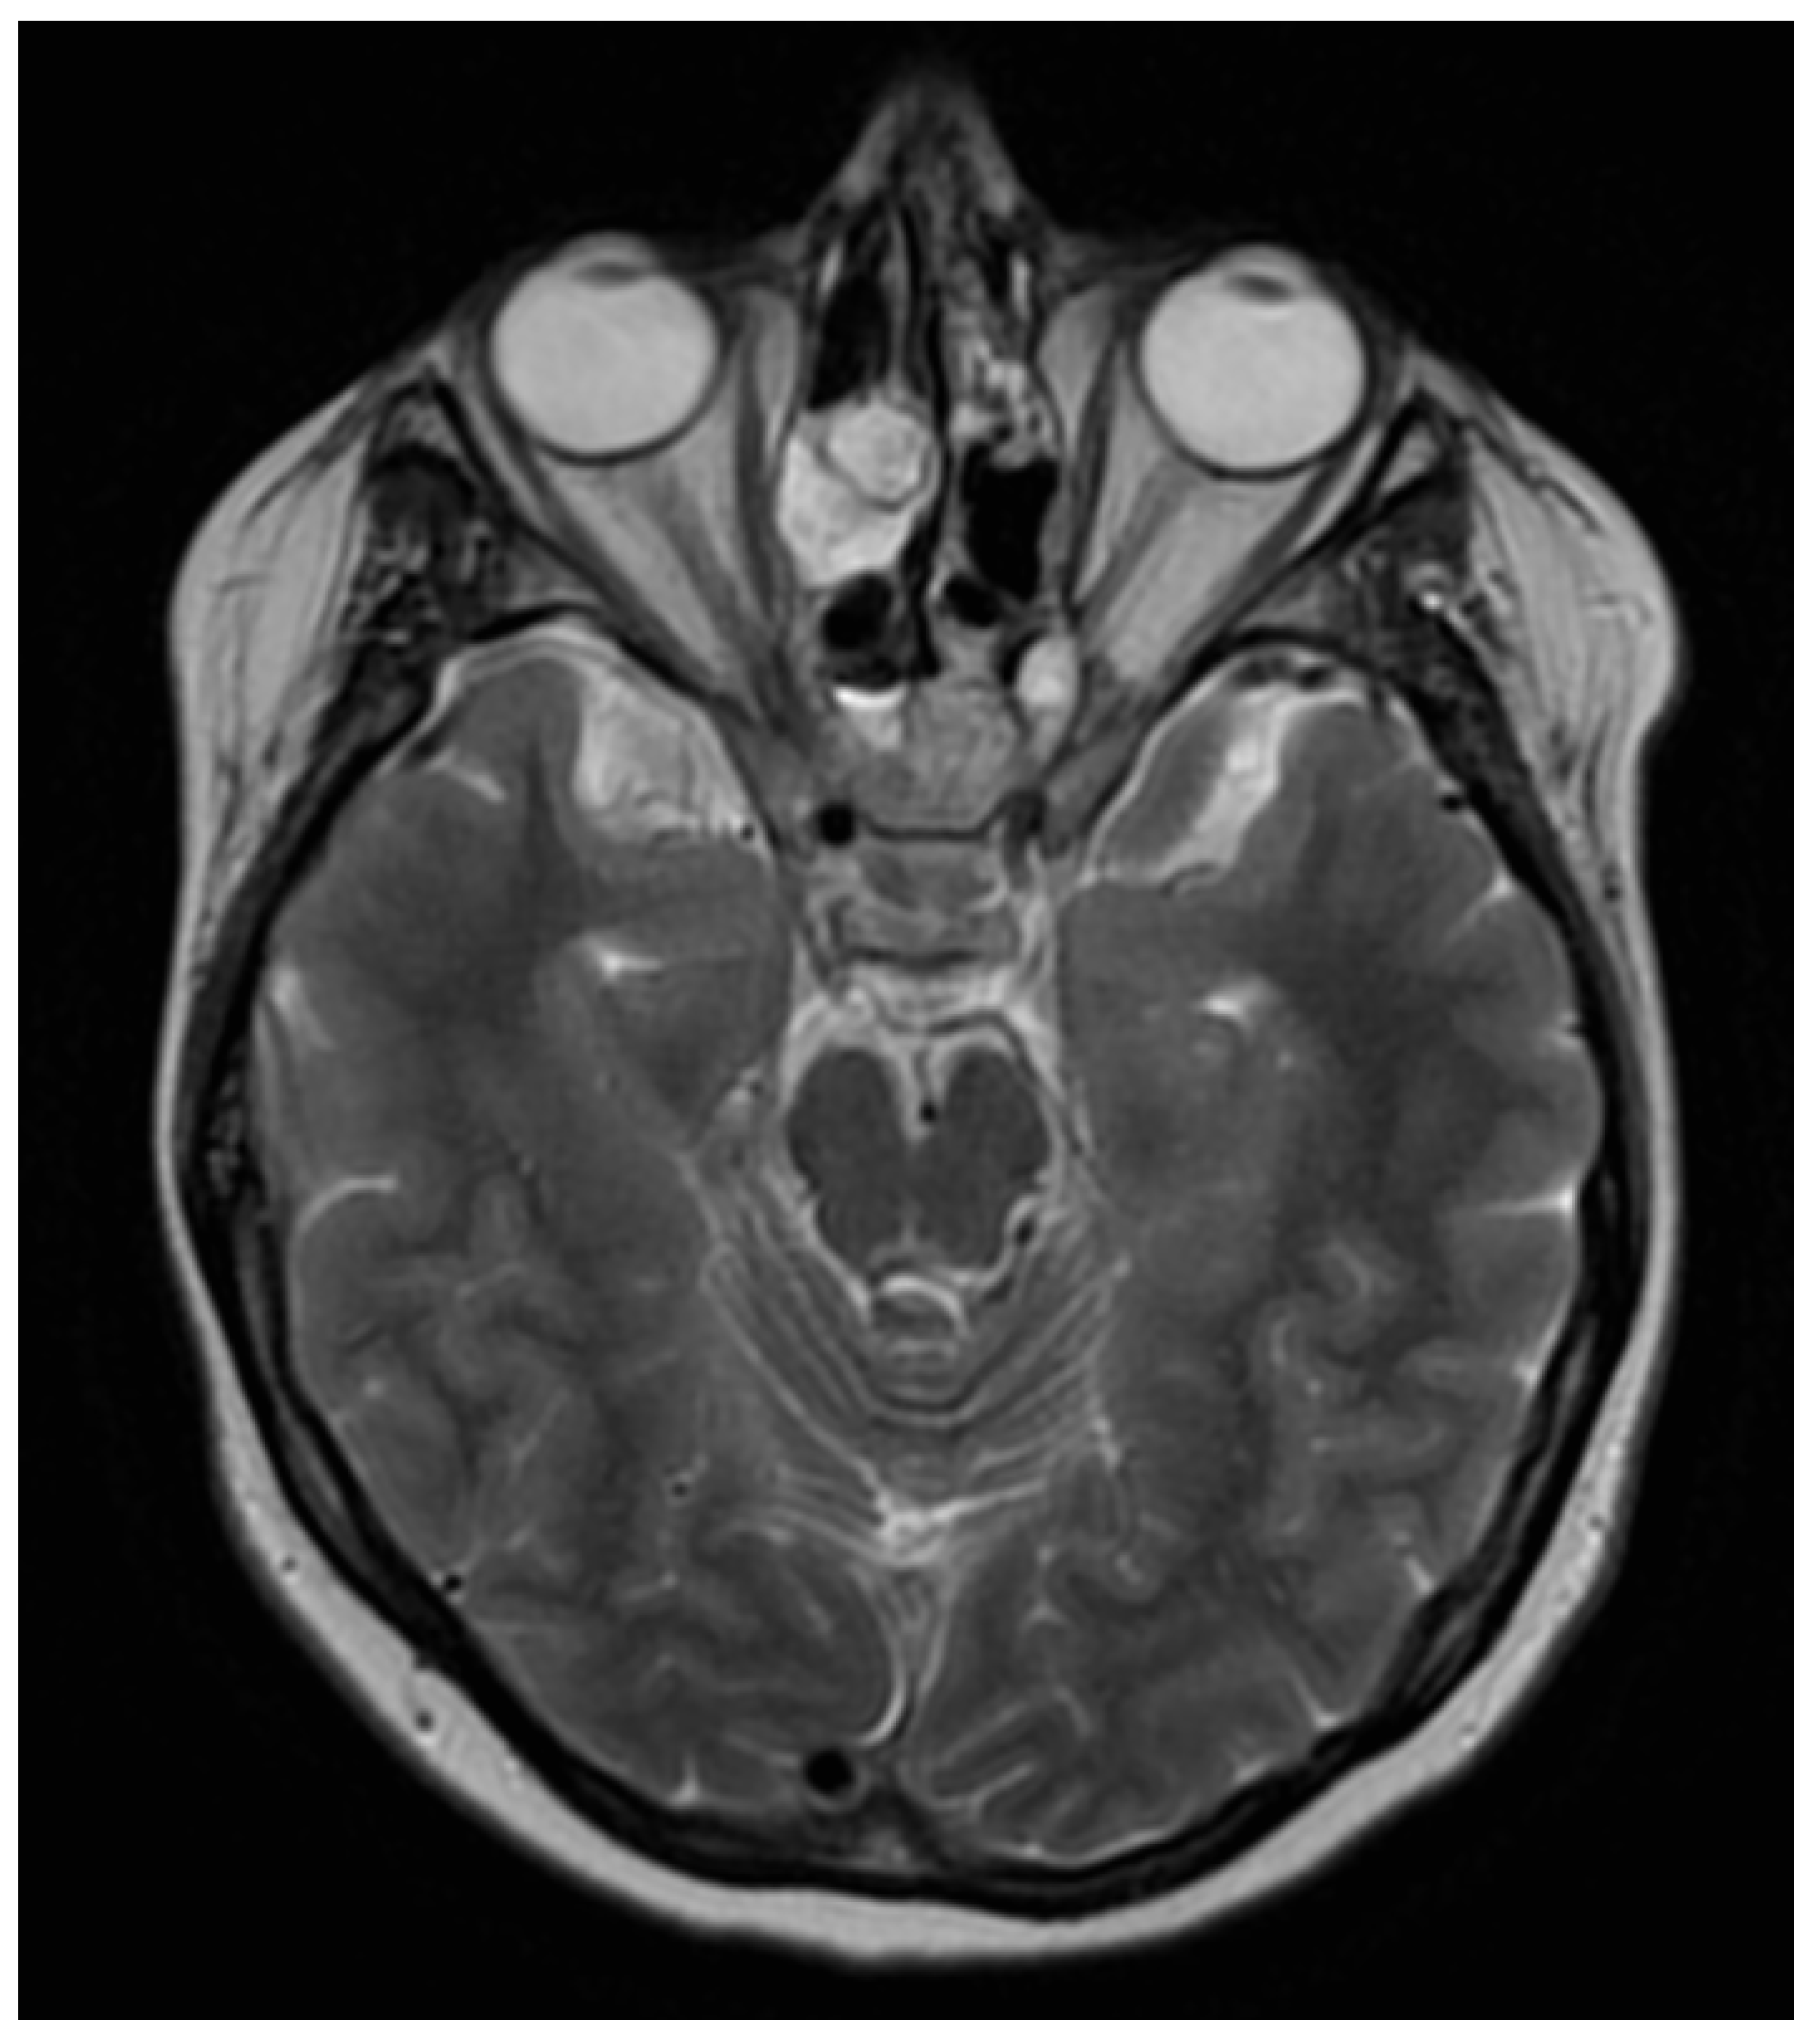

In November 2020, the patient presented with a sudden loss of vision in the LE limited to light perception due to the compression of the left optic nerve with inflammatory/granulomatous masses extending from the ethmoid (Figure 12). Methylprednisolone and immunoglobulins were administered intravenously. Due to the high activity of the disease and the high risk of vision loss in the RE, rituximab was introduced. Four weekly RTX infusions were given with a subjective improvement of vision. In the last week of the treatment, a fistula formed in the ethmoid lamina, causing the rhinorrhea of the cerebrospinal fluid through the right nasal passage (Figure 13). Subsequently, RTX treatment was complicated by the reactivation of opportunistic infections: CMV and HSV1 (high transaminases). Therefore, ganciclovir was introduced.

Figure 12. MRI of axial plane—a compressive mass in the left retrobulbar space causing the compression of the left optic nerve.